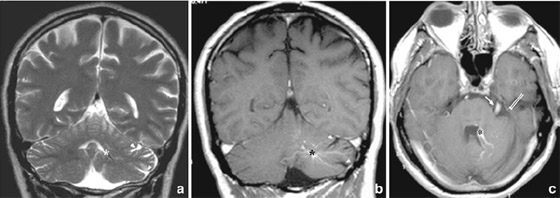

وأوضح الأطباء أن ما حدث كان بسبب تناول الرجل لحم الخنزير المقدد غير المطبوخ جيدًا، وفقا لما ذكرت شبكة بريطانية، حيث كشف تصوير بالأشعة المقطعية أجراه أطباء لدماغ الرجل، عن بيوض الدودة الشريطية، كما تم تشخيص المريض بداء الكيسات المذنَّبة العصبي.

يشار إلى أن هذا الداء يعدّ نوعاً خاصاً من داء الكيسات المذنبة، ويحدث بسبب عدوى بالشريطية الوحيدة، وهي شريطية حقيقية (Eucestoda) تُوجد في الخنازير، والتي يمكن أن تصل إلى الأنسجة مثل العضلات والدماغ. في حين نفى المريض تناول طعام نيء أو وجبات من الشارع، إلا أنه اعترف بعادة تناول لحم الخنزير المقدد المطبوخ بشكل خفيف وغير المقرمش معظم حياته. في حين أكد الباحثون أن الرجل تعرض للعدوى الذاتية، بعد عدم غسل اليدين بشكل لائق.